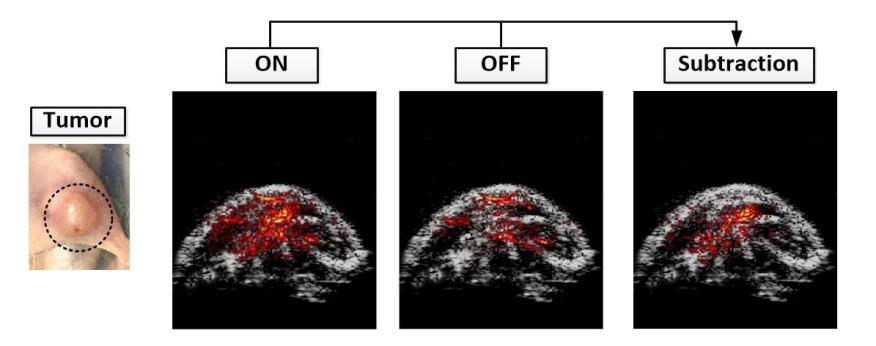

圖1:(a).基于細菌遞送體系的腫瘤靶向成像示意圖;(b)基因編碼開關蛋白在ON、OFF兩種狀態下,小鼠腫瘤區域光聲成像結果,以及二者差值實現背景噪音抑制結果;(c)大腸桿菌F469W載體內,多個蛋白開關周期光聲信號由ON到OFF可逆變化結果。